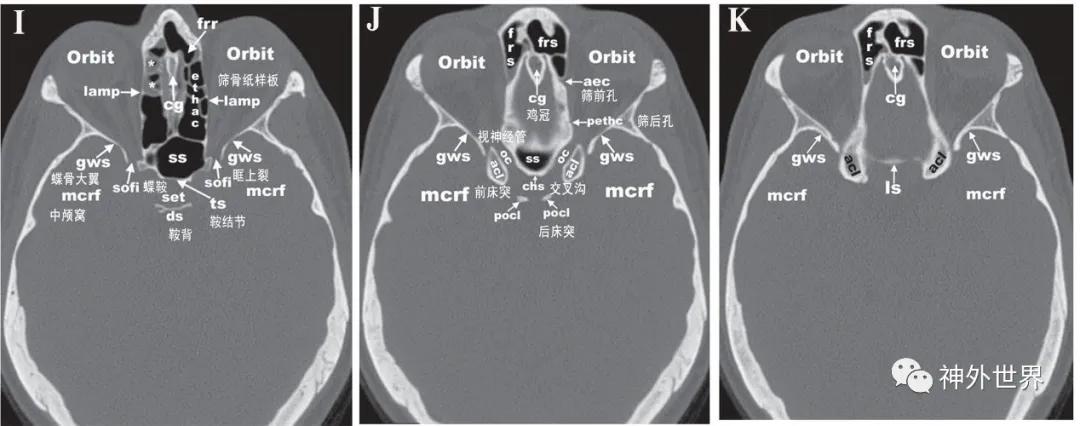

图3:颅底CT骨性横断面影像解剖